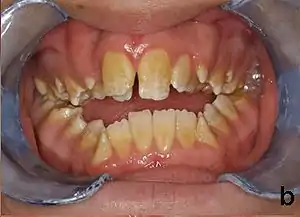

| Amelogenesis imperfecta, hypoplastic type. Note the association of pitted enamel and open bite. | |

People with amelogenesis imperfecta may have teeth with abnormal color: yellow, brown or grey; this disorder can affect any number of teeth of both dentitions. Enamel hypoplasia manifests in a variety of ways depending on the type of AI an individual has (see below), with pitting and plane-form defects common.[4] The teeth have a higher risk for dental cavities and are hypersensitive to temperature changes as well as rapid attrition, excessive calculus deposition, and gingival hyperplasia.[5] The earliest known case of AI is in an extinct hominid species called Paranthropus robustus, with over a third of individuals displaying this condition.[6]